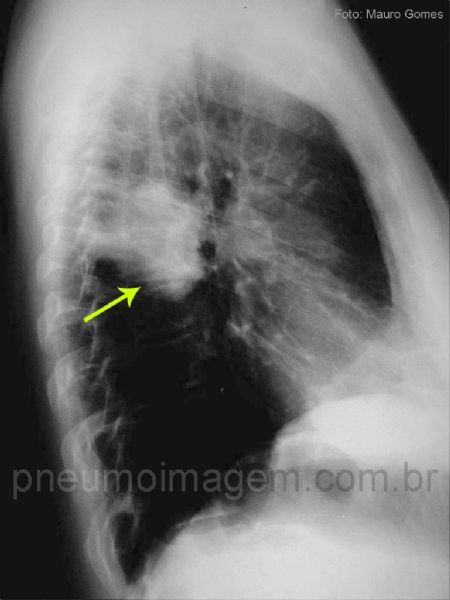

Nesta radiografia em perfil é possível observar que a lesão (seta amarela) se localiza no segmento apical do lobo inferior esquerdo.

In this lateral view you can see that the lesion (yellow arrow) is located in the apical segment of the left lower lobe.